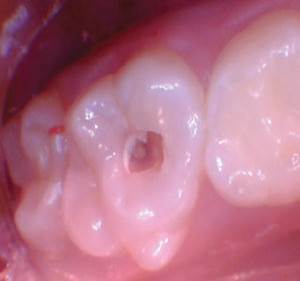

Caso 1

Un paciente de 8 años presentó descomposición de OD en un primer molar primario con síntomas de pulpitis reversible. El diente fue el tratamiento planificado para una restauración de OD con Activa Bioactive Restorative (Pulpdent). Tras la excavación por descomposición, se produjo una exposición pulpar que requirió una pulpotomía terapéutica. Debido a la edad del paciente, me sentí cómodo con una pulpotomía terapéutica con Biodentine (Septodont) seguida de una restauración estética. Si el paciente hubiera tenido entre cuatro y cinco años, me habría restaurado con una corona de acero inoxidable debido a su historial comprobado de longevidad.

Figura 1 Vista preoperatoria del primer molar primario superior. |